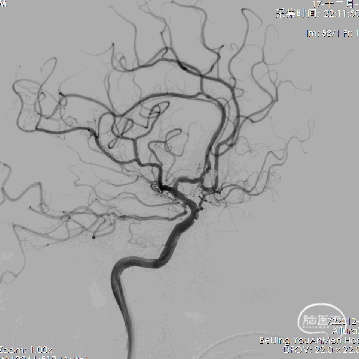

13、支架置入后左侧大脑前动脉血流好转。

14、栓塞后造影。

栓塞后正位造影

术后给予替罗非班静脉泵入,术后第二天进行MRA。